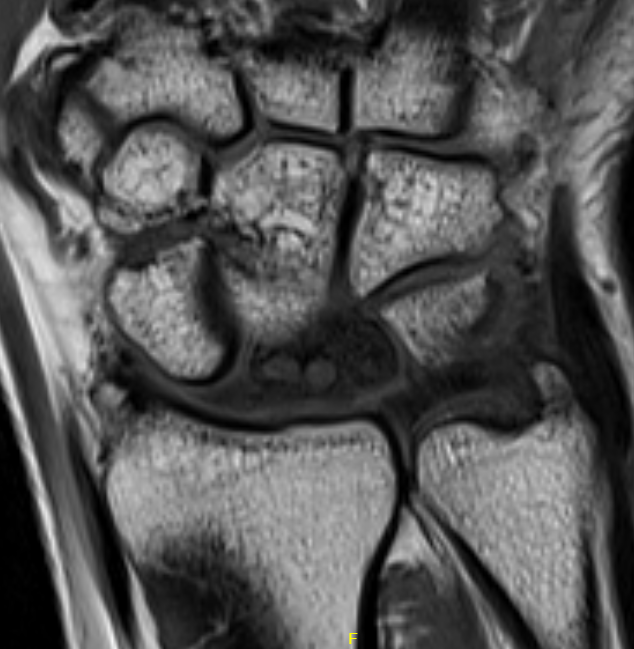

MRI

Avascular lunate on MRI

Avascular lunate with some cystic change on the capitate